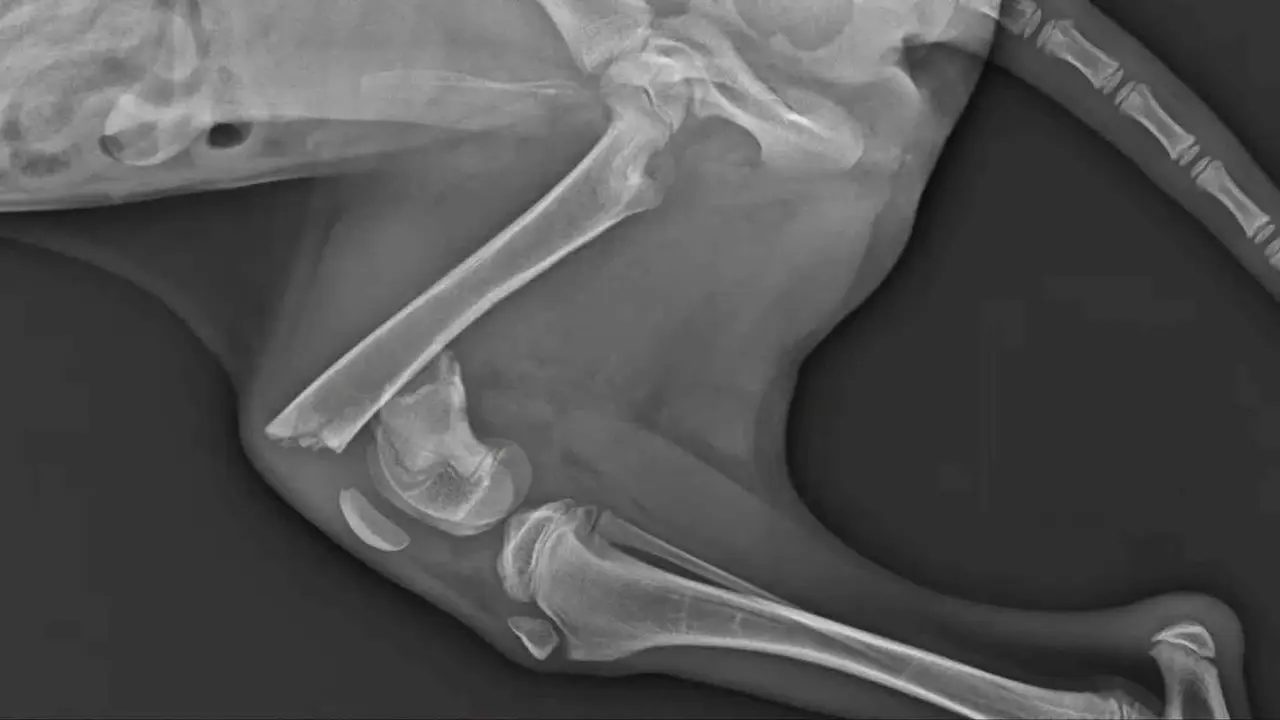

El sangrado de encías espontáneo o tras mínimo contacto, así como la presencia de heridas purulentas en la zona facial, son manifestaciones físicas que permiten diferenciar un dolor dental significativo de otras patologías menos invasivas. El examen veterinario, incluyendo radiografías dentales, es esencial para confirmar el diagnóstico y descartar otras causas como trauma o tumores.

En la práctica clínica, distinguir entre estos tres tipos de dolor es clave para definir el tratamiento adecuado. Un absceso de muela requiere radiografías dentales y a menudo extracción o tratamiento endodóntico; la gingivitis se aborda con limpieza dental y control de placa; y el dolor mandibular necesita evaluación articular y muscular, a menudo asociado a trauma u otras patologías ortopédicas o neurológicas.

Es común que el veterinario confirme estas observaciones mediante palpación suave de las zonas faciales. Los perros con abscesos radiculares suelen retirarse, gemir o tensar la cabeza cuando se presiona el lado afectado, lo que ayuda a localizar la región exacta del problema. Aunque estos signos externos son altamente orientativos, la confirmación definitiva requiere radiografías dentales intraorales.